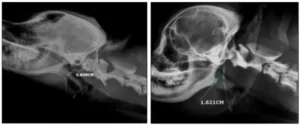

- معاینه بالینی: بررسی تنفس، خروپف و ساختار بینی.

- تصویربرداری: رادیوگرافی یا سیتیاسکن برای بررسی راههای هوایی.